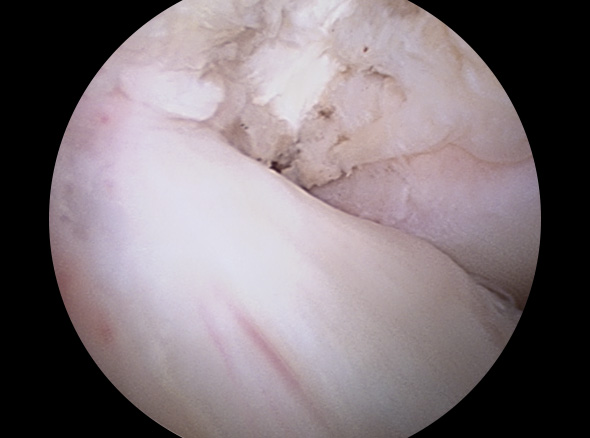

경골과 대퇴골 사이에 남아 있는 전방십자인대 제거

경골과 대퇴골 사이에